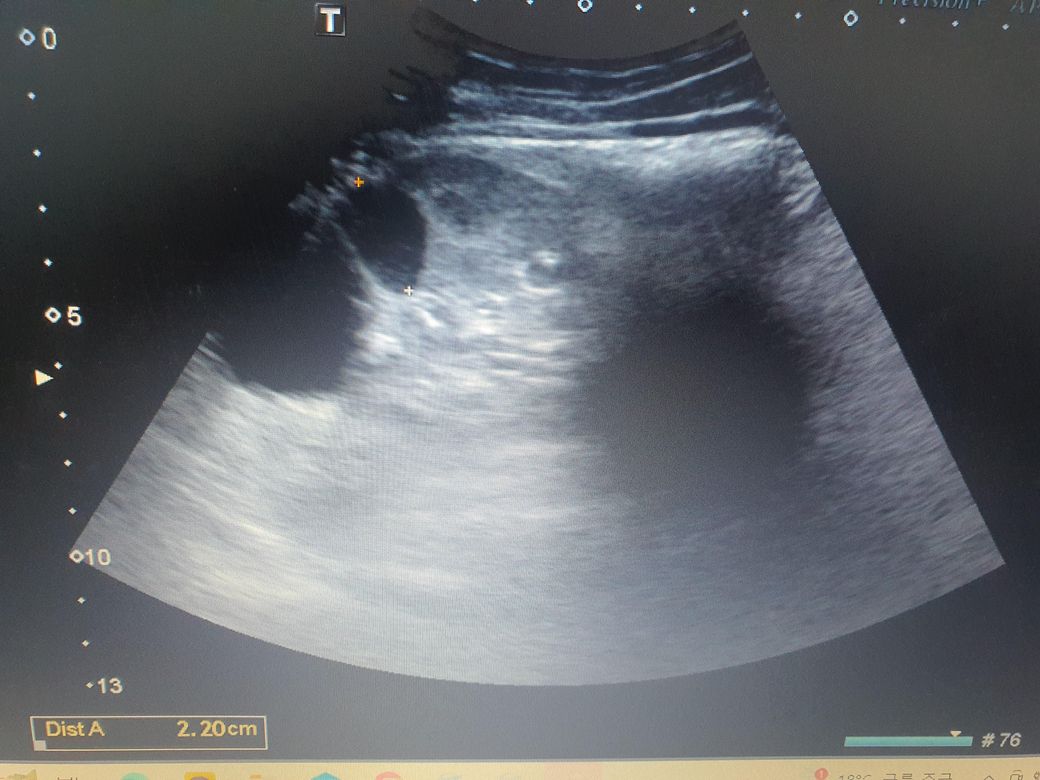

이거 신장 낭종이 1개인건지?2개인건지?

제 신장인데 3.6cm가 있다고 하더라구요

의사분은 몇 개라고는 알려주진 않으셨는데

초음파CD를 받아서 집에 와보니 3.6cm옆에 다른 사진에 2.2cm라고 되어 있어서 궁금합니다.

사진에 보이는 낭종은 두 개이고, 각각 3.6cm와 2.2cm 크기를 가지고 있습니다.

신장 낭종이 2개가 맞습니다.

다만 단순 낭종으로 보이며 암으로 변이 가능성은 없습니다.

혹시라도 걱정이 되신다면 1년마다 신장 초음파 해보시는 것을 추천드립니다.